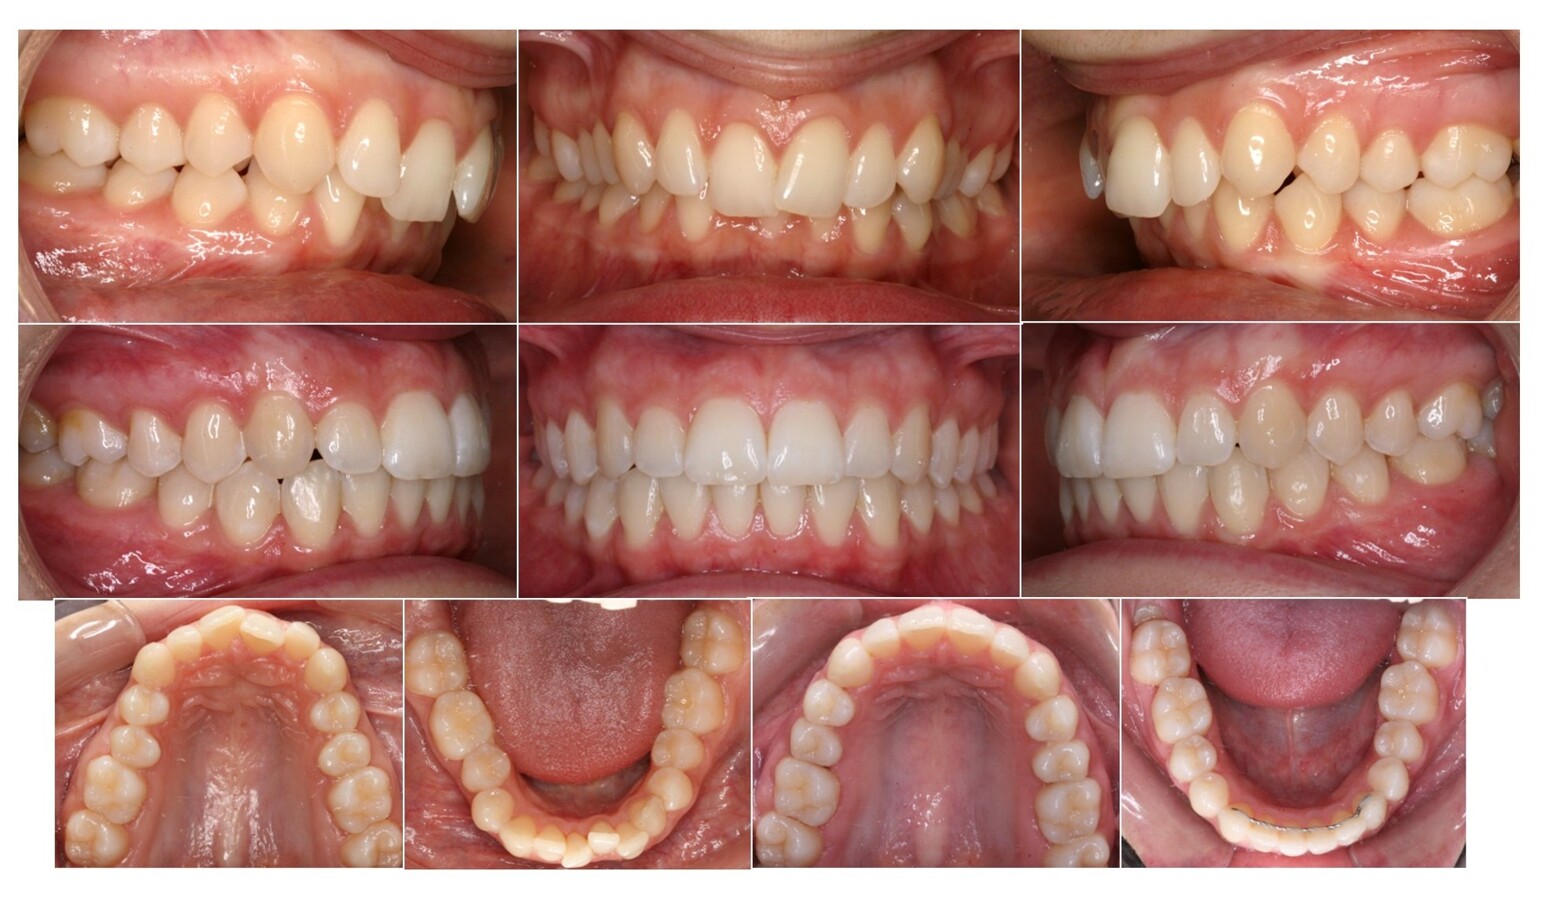

El papel del crecimiento vertical del hueso alveolar sorprende en casos como éste, donde hemos tratado una joven de 16 años de Clase II mandibular con brackets, arcos y elásticos intermaxilares cortos y fuertes. Antes y después.

Cambios faciales notables en esta paciente a pesar de su edad al inicio del tratamiento de ortopedia mandibular, gracias al desarrollo vertical del hueso alveolar y el "post-puberal growth spurt" característico en algunas mujeres después de la adolescencia.